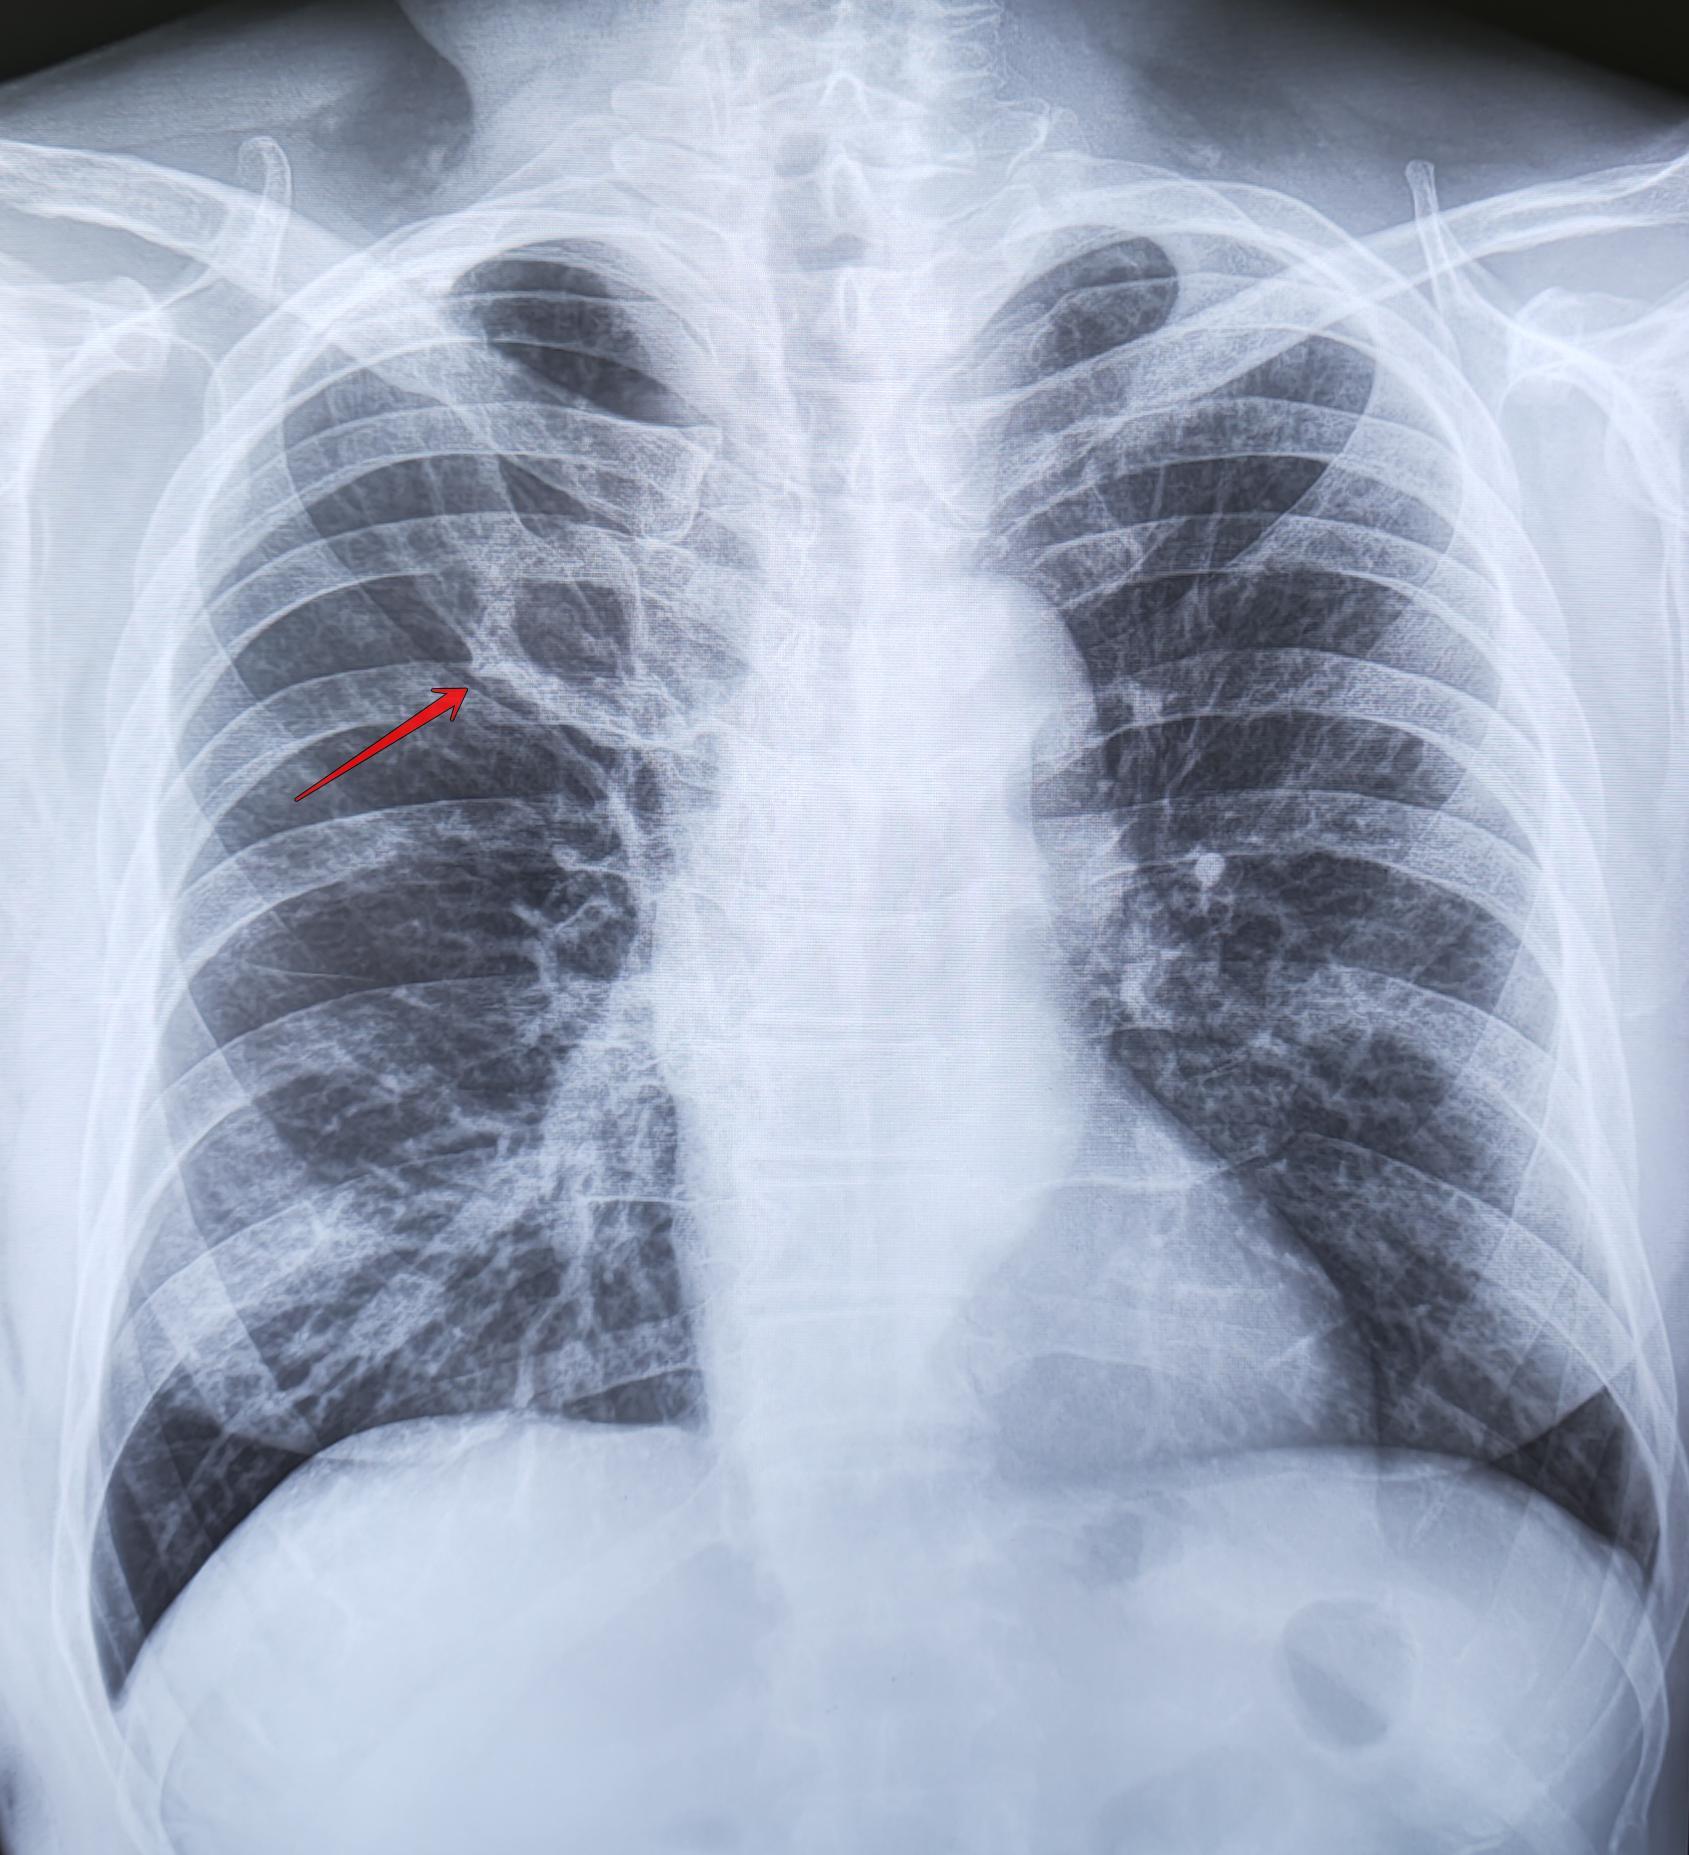

Ребро Люшка

Ребро Люшка - врожденная аномалия развития ребра в виде удвоения его переднего отдела

-Иногда ошибочно принимается за опухоль или фиброзные изменения.